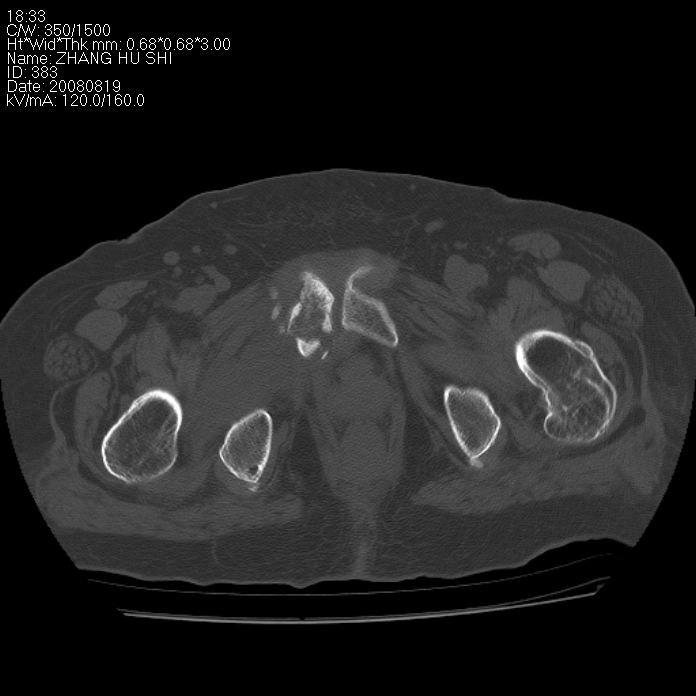

标题: CT15287:女 93岁 右髋关节疼痛 原左侧粗隆间骨折 CT发现右耻 [打印本页]

标题: CT15287:女 93岁 右髋关节疼痛 原左侧粗隆间骨折 CT发现右耻

支持转移并周围软组织侵犯右闭孔内肌侵犯,但tb不能完全除外。